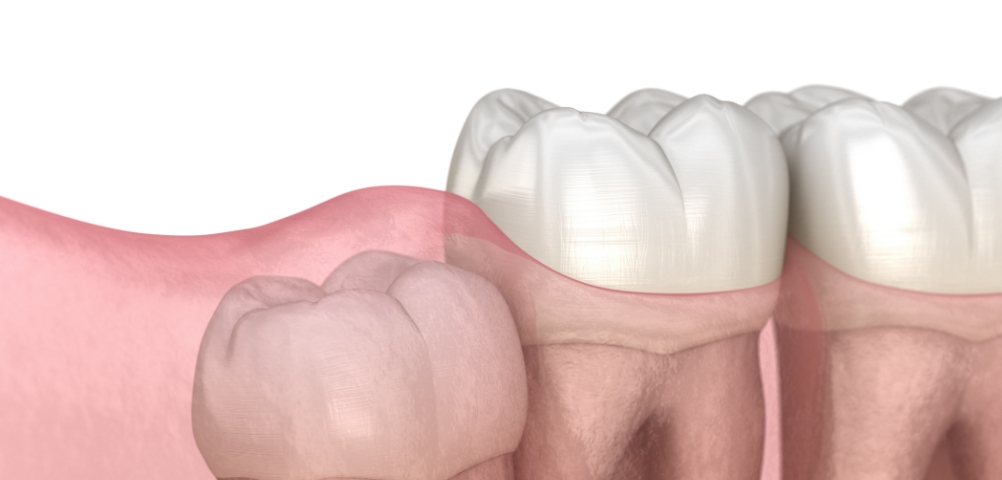

3D CT로 사랑니의 방향, 신경 위치, 주변 치아와의 관계를 세밀하게 확인한 뒤 필요한 경우에 한해 발치를 진행합니다.

불필요한 조직 손상을 최소화하는 방식으로 부담을 줄이며, 환자분이 보다 편안하게 회복하실 수 있도록 돕고 있습니다.